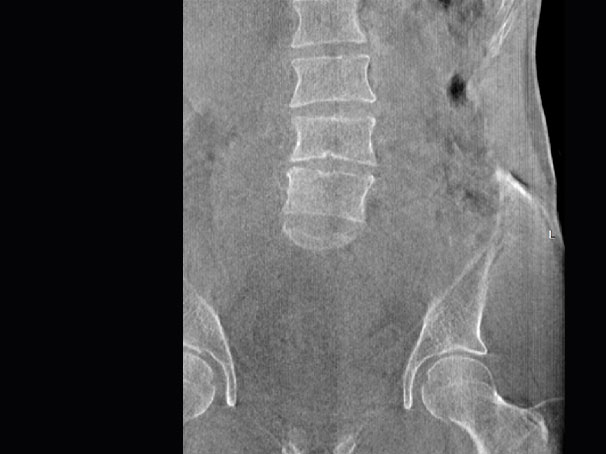

髋关节